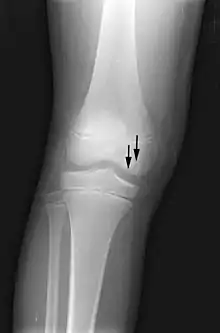

X-ray images of avascular necrosis in the early stages usually appear normal. In later stages it appears relatively more radio-opaque due to the nearby living bone becoming resorbed secondary to reactive hyperemia.[2] The necrotic bone itself does not show increased radiographic opacity, as dead bone cannot undergo bone resorption which is carried out by living osteoclasts.[2] Late radiographic signs also include a radiolucency area following the collapse of subchondral bone (crescent sign) and ringed regions of radiodensity resulting from saponification and calcification of marrow fat following medullary infarcts.

The intravertebral vacuum cleft sign (at white arrow) is a sign of avascular necrosis. Avascular necrosis of a vertebral body after a vertebral compression fracture is called Kümmel's disease.[20]